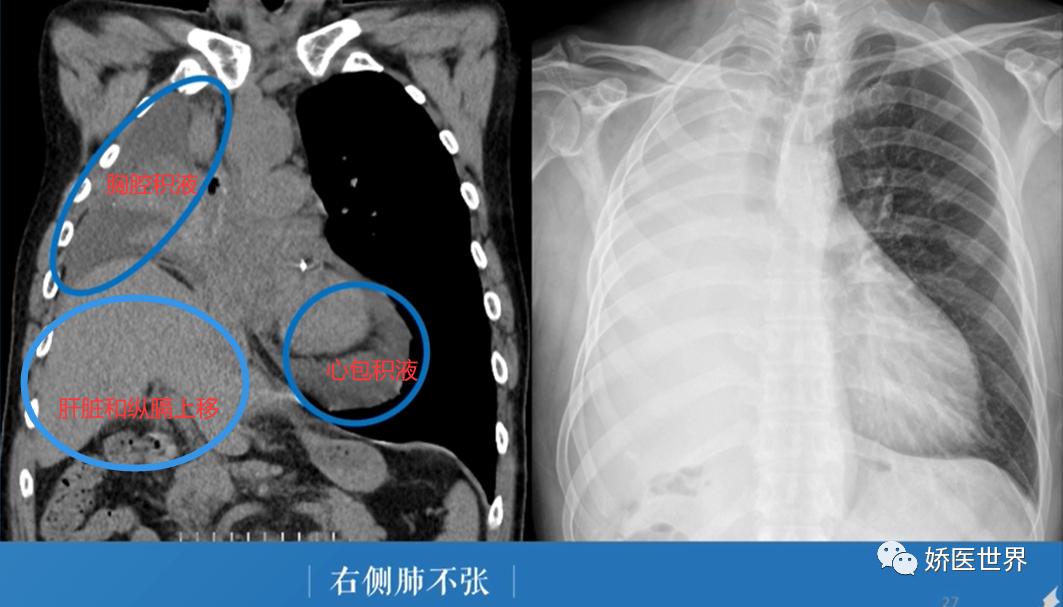

②右侧肺不张:右侧肺野密度增高,肺纹理消失,纵膈及气管向右侧移位,右侧膈肌及肝脏明细上移。同时还可以看到右侧胸腔积液和心包积液。由于右侧的胸腔积液会使纵膈向左移位,心包积液会使心影向左侧扩大,这样抵消了一部分肺不张牵拉纵膈和心脏的作用,使得纵膈和心影右移的表现并不明显。